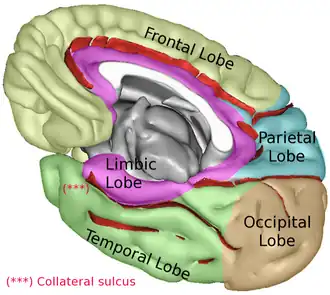

| Lobes of the cerebral cortex (right hemisphere view) | |

Medial surface. Five lobes visible. | |

The lobes of the brain are the four major identifiable regions of the human cerebral cortex, and they comprise the surface of each hemisphere of the cerebrum.[1] The two hemispheres are roughly symmetrical in structure, and are connected by the corpus callosum. Some sources include the insula and limbic lobe but the limbic lobe incorporates parts of the other lobes. The lobes are large areas that are anatomically distinguishable, and are also functionally distinct. Each lobe of the brain has numerous ridges, or gyri, and furrows, sulci that constitute further subzones of the cortex.[2] The expression "lobes of the brain" usually refers only to those of the cerebrum, not to the distinct areas of the cerebellum.

Limbic lobe

The limbic lobe is an arc-shaped region of cortex on the medial surface of each cerebral hemisphere of the mammalian brain, consisting of parts of the frontal, parietal and temporal lobes. The term is ambiguous, with some authors including the paraterminal gyrus, the subcallosal area, the cingulate gyrus, the parahippocampal gyrus, the dentate gyrus, the hippocampus and the subiculum;[11] while the Terminologia Anatomica includes the cingulate sulcus, the cingulate gyrus, the isthmus of cingulate gyrus, the fasciolar gyrus, the parahippocampal gyrus, the parahippocampal sulcus, the dentate gyrus, the fimbrodentate sulcus, the fimbria of hippocampus, the collateral sulcus, and the rhinal sulcus, and omits the hippocampus.

Insular cortex

The insular cortex is a portion of the cerebral cortex folded deep within the lateral sulcus (the fissure separating the temporal lobe from the parietal and frontal lobes). The insular cortex has an important function for sending axons to the amygdala and responding to tones and somatosensory stimulation.[12]